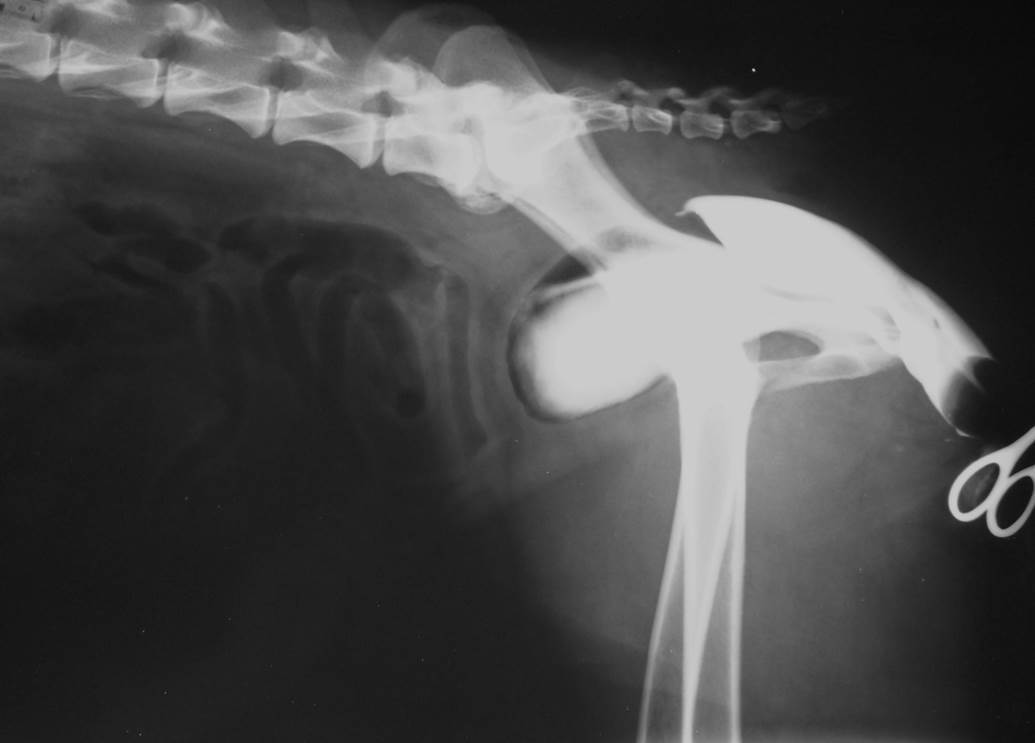

Case Flossie

Discuss this case?

•Normal IVU & RVU showing no evidence of

–ectopic ureter

–megaureter

–hydronephrosis

–bladder hyoplasia

–urethral anomaly

–uroliths